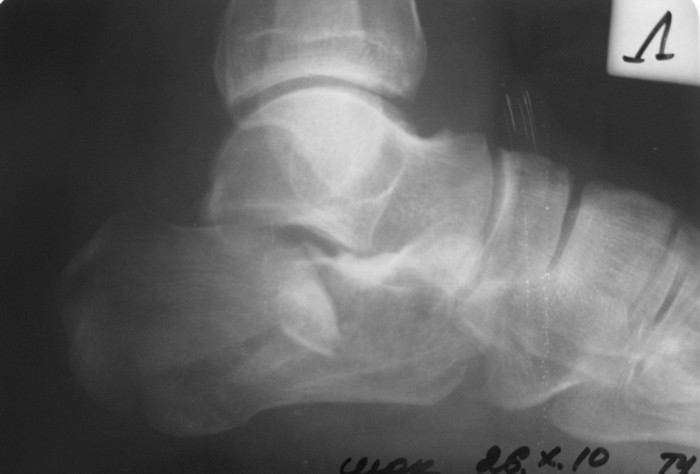

Операция проведена на 14е сутки после травмы. Фиксация блокируемой пластиной. Трудности - сложность репозиции; необходимость костной пластики (уложен измельченный трансплантат из гребня подвздошной кости 4,5х1,5х1см); множество мелких отломков; большой фрагмент наружной кортикальной пластинки, закрывающий картину в суставе.

followup1.jpg

По-моему, репозиция достигнута